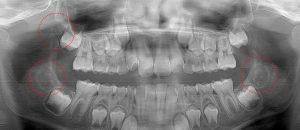

This 34 year old patient has all four third molars present (circled) and fully erupted into occlusion. They appear disease free…but are difficult to keep clean. 3rd molars are the most likely teeth to decay or have gum disease with a >98% probability that decay and gum disease will occur around all four teeth over this patient’s life time.